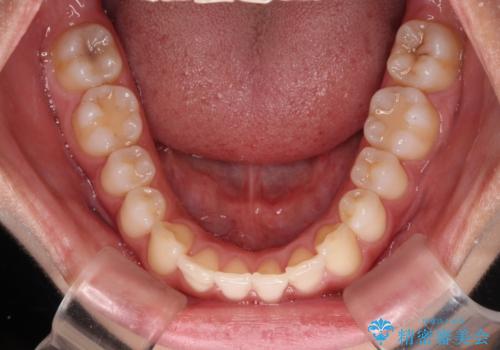

前歯の重なりをインビザライン・モデレートで矯正治療

- インビザライン・モデレート

- 1年2ヶ月

インビザライン・モデレートは、製作できるアライナーの枚数に制限があるため、移動可能な量に限りがあるものの、インビザライン・ライトよりも枚数が多いため、幅広い症例に対応可能です。